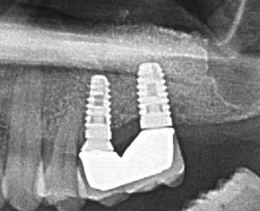

ソケットリフト症例(治療前後のCTもしくはパノラマ写真)

↓

↓